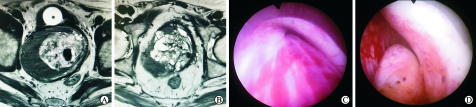

入院后完善生化检查:血红蛋白157 g/L,tPSA 5.622 ng/mL,fPSA/tPSA比值0.44。经腹泌尿系B超示:膀胱后下方可见一囊实性包块,囊壁可见多发壁结节,前列腺来源占位?前列腺位置发育异常?盆腔磁共振成像(magnetic resonance imaging, MRI):前列腺结构不清,局部见巨大囊实性病变,大小约10.3 cm×7.3 cm×10.0 cm, 内见T1高信号。前列腺囊实性病变伴出血,性质待定(图1A、B)。膀胱镜下观察:膀胱黏膜清晰,小梁增生明显,双侧输尿管口可见;膀胱颈受外压抬高,未见明显前列腺侧叶,精阜受推挤左移(图1C、D)。前列腺活检提示:(前列腺肿物)良性前列腺组织,部分为前列腺腺体,部分组织衬覆尿路上皮,未见肿瘤性病变。前列腺结节穿刺薄层液基细胞学检查(thinprep cytologic test, TCT)涂片仅见少量单个核细胞,未见确切肿瘤细胞及精子。

A: 前列腺多房囊腺瘤MRI平扫:前列腺结构不清,局部见巨大囊实性病变,大小约10.3 cm×7.3 cm×10.0 cm, 内见T1高信号;B:前列腺囊实性病变伴出血,性质待定;C:膀胱镜探查:膀胱镜下观察膀胱黏膜清晰,小梁增生明显,双侧输尿管口可见,膀胱颈受外压抬高,未见明显前列腺侧叶;D:精阜受推挤左移。

图1 巨大多房性前列腺囊腺瘤(GMPC)患者盆腔磁共振成像(MRI)及膀胱镜下观